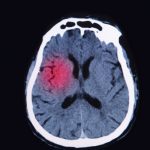

Traumatic brain injury (TBI) risk high in seniors and rising, may initiate Alzheimer-like neurodegeneration

Traumatic brain injury (TBI) risk is high in seniors and continues to rise, prompting researchers to believe that it may initiate Alzheimer-like neurodegeneration. Traumatic brain injury is a major cause of death and disability in the U.S., according to the Centers for Disease Control and Prevention (CDC). Daily, 138 Americans die from TBIs, while many of the survivors are often plagued with lifelong disability and face numerous challenges.

A TBI occurs when there is a blow, bump, or jolt to the head region, disrupting the normal function of the brain. TBIs can range in severity and not all head injuries result in a TBI. A mild version of a TBI is a concussion, which is a common occurrence.